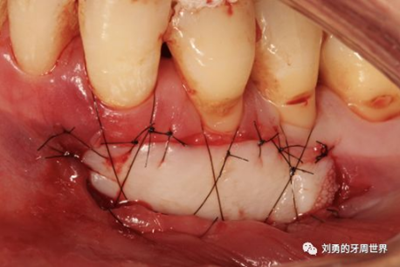

傳統(tǒng)的縫合方式非常簡(jiǎn)單,比如:

該方式齦瓣固定的效果差,術(shù)后血供差,為了改善血供,我們提倡下面的改良縫合方式,血供更好,成功率更高,如下圖:

通過(guò)用縫線壓迫的方式固定,術(shù)后愈合的過(guò)程齦瓣始終與受區(qū)骨膜貼合,而不會(huì)移動(dòng)。